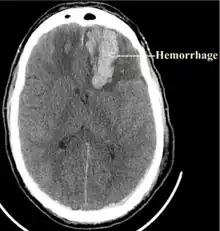

Powassan virus infection is rarely diagnosed as a cause of encephalitis; however, when it is, Powassan encephalitis is severe, and neurologic sequelae are common.[7] Powassan encephalitis has symptoms compatible with acute disseminated encephalomyelitis, oftentimes making it difficult to diagnose.[7] Powassan virus encephalitis is a challenge to diagnose because there are only a few laboratories that offer testing, the most effective being serologic testing.[23]

There are currently no medications or approved vaccines to treat or prevent the POWV. People affected by Powassan virus generally first show symptoms 1 to 3 weeks after infection.[5] The initial symptoms include fever, headache, nausea, occasional confusion, and weakness.[6] With severe Powassan illnesses the victims should be hospitalized, because the symptoms do worsen. If not treated, symptoms could extend to meningoencephalitis, which may include: seizures, aphasia, cranial nerve palsies, paresis and altered mental status.[5][6] Currently, the best ways to treat POWV illnesses include medications to reduce brain swelling, respiratory support and intravenous fluids.[6] About 10% of POWV encephalitis cases are fatal and half the survivors have permanent symptoms that affect their brain.[17] There were 33 confirmed cases of Powassan virus infection in the U.S. between 2001 and 2010.[5]

A rare case of a five-month-old Connecticut infant boy contracting Powassan virus infection was published in 2017. He survived with normal motor and verbal development on follow-up at the age of 10 months, but a head MRI showed severely abnormal brain conditions, including scarring (gliosis) and softening (encephalomalacia) in the thalamus and basal ganglia on both sides, and volume loss and early mineralization in the left basal ganglia.[24]